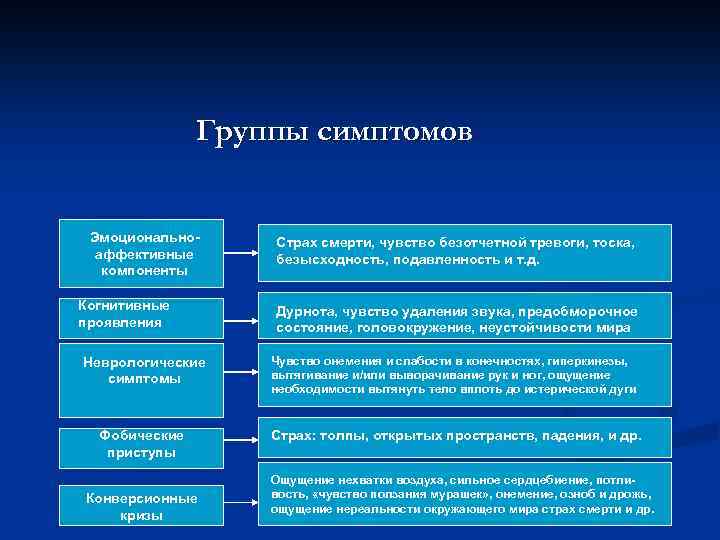

Группы симптомов Эмоциональноаффективные компоненты Когнитивные проявления Страх смерти, чувство безотчетной тревоги, тоска, безысходность, подавленность и т. д. Дурнота, чувство удаления звука, предобморочное состояние, головокружение, неустойчивости мира Неврологические симптомы Чувство онемения и слабости в конечностях, гиперкинезы, вытягивание и/или выворачивание рук и ног, ощущение необходимости вытянуть тело вплоть до истерической дуги Фобические приступы Страх: толпы, открытых пространств, падения, и др. Конверсионные кризы Ощущение нехватки воздуха, сильное сердцебиение, потливость, «чувство ползания мурашек» , онемение, озноб и дрожь, ощущение нереальности окружающего мира страх смерти и др.